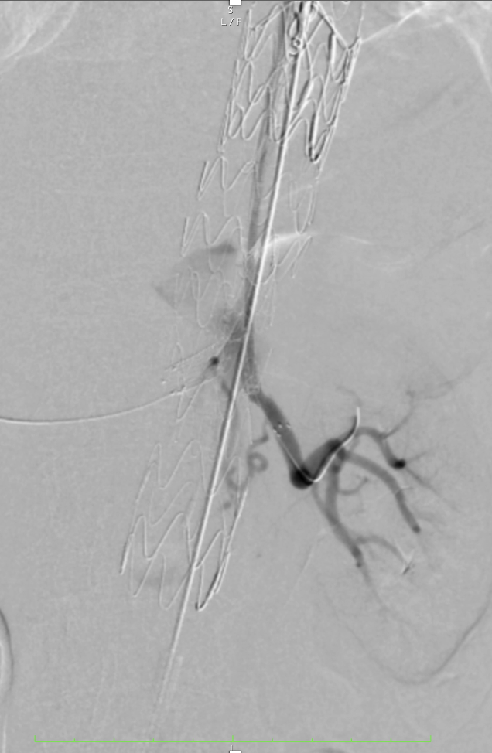

超选SMA,桥接8-100mm Viabahn,内衬8-60mm Absolute裸支架

超选CA,桥接8-100mm Viabahn

超选RRA烟囱支架,桥接6-100mm+6-50mm Viabahn

超选LRA烟囱支架,桥接6-100mm Viabahn

右侧:16-16-140mm Excluder髂腿;

左侧:16-16-120mm Excluder髂腿

术后造影